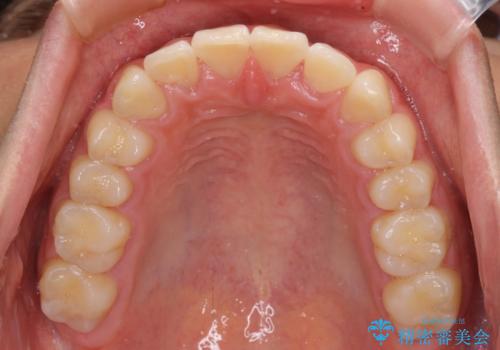

深い咬み合わせとデコボコ ワイヤー矯正で短期治療

- 前歯のデコボコを改善したいとのことで来院された患者様です。

インビザラインでの治療も可能でしたが、深い咬み合わせと奥歯の咬み合わせを改善するにあたり、ワイヤー矯正の方が治療期間を短縮できると判断し、ワイヤー矯正をお勧めしました。

結果として、1年かからずに奥歯の咬み合わせを改善することができました。